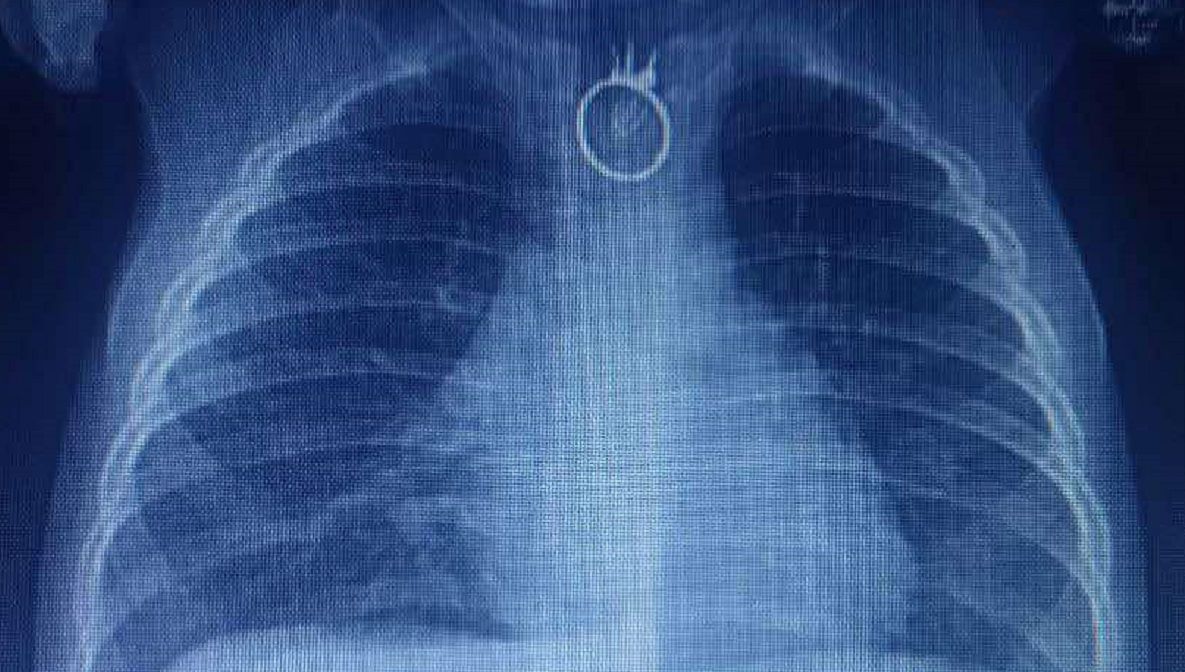

До Центру дитячої медицини «швидка» привезла з Нового Роздолу 10-місячного хлопчика зі слинотечею, задишкою, порушенням ковтання. Рентген, який зробили дитині у місцевій лікарні, виявив сторонній предмет у стравоході, тож малюка відразу скерували до Львова, в лікарню «Охматдит».

Батьки запідозрили, що син, мабуть, щось проковтнув, коли він став дуже неспокійним. У нього була постійна слинотеча, з’явилися порушення дихання та задишка. Малюк не міг нічого ковтати. У лікарні в Новому Роздолі малюку зробили рентген, на якому й побачили сторонній предмет. Дитину негайно каретою швидкої допомоги доставили до Центру дитячої медицини, повідомили у медзакладі.

Сторонній предмет у хлопчика виявили під час рентгену

«Відразу після госпіталізації, о другій ночі, ми взяли дитину в операційну і провели ригідну езофагоскопію з видаленням стороннього тіла. Це був іграшковий перстень. Все пройшло успішно. Єдине, що перстень трохи пошкодив стравохід», – каже дитячий хірург Олександр Колодій.